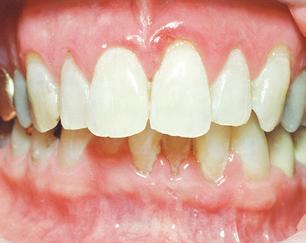

THE PERIO-ORTHO SYSTEMIC LINK

The perio-ortho systemic link has been clearly connected through the years.

As

healthcare providers, we should focus on both disease prevention and treatment modalities when dealing with periodontal disease.

It is now clear that orthodontic health is vital for periodontal and systemic health. Therefore, orthodontic treatment should be one of the treatment options considered in prevention plans, as well as restorative plans in dentistry. Evidence based dentistry has shown that more than just three millimeters of crowding can be a host factor for periodontal disease. Therefore, preventative treatment to avoid periodontal issues should consist of placing the teeth in proper alignment, including reduction or elimination of crowding. Research has also shown that there is significantly greater plaque accumulation in crowded areas. Interestingly, research also indicates that the bacteria present in crowded areas consistently represents more species of periodontopathogens than bacteria from non-crowded regions. The pathogens are more virulent in the areas that are more crowded because they become anaerobic, meaning they grow in the absence of oxygen. As plaque accumulation increases subgingivally, or beneath the gums, the amount of periodontopathogens increases. 2

If we can reduce crowding, then we can reduce aggressive periodontal pathogenic bacteria, which can subsequently decrease the risk of periodontal disease as well as the inflammatory disease processes in the rest of the body. Our currently preferred options for reducing crowding include traditional braces and clear aligner therapy, such as Invisalign®